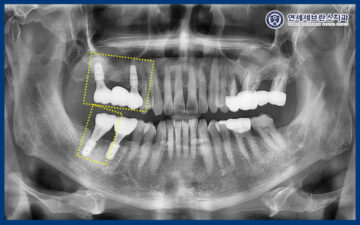

파노라마 사진을 촬영해 보니,

오른쪽 위 치아 2개와 아래 맨 뒤 치아의

잇몸뼈 소실로 치주염이 진행된 것을

확인할 수 있었습니다.